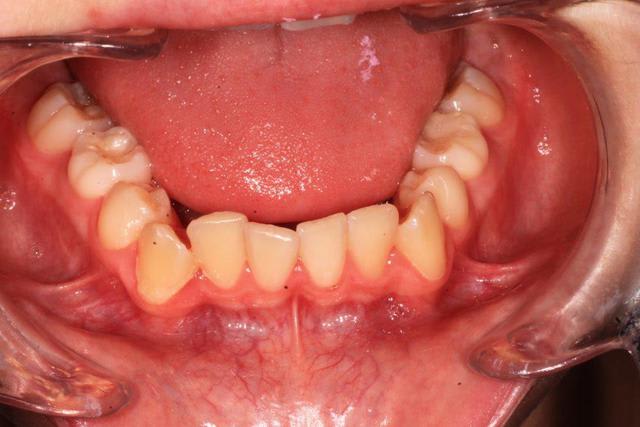

jeune homme de 12 ans 1/2 , consulte pour luxation atm et demande de gouttière.

Au niveau ODF , il y a une cl 2 bout a bout avec supra, malposition canine.

quelques documents :